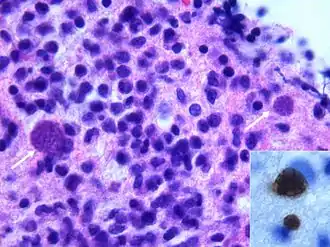

On décrit de rares cas où un sujet VIH+, sans immunité anti-toxoplasmique (pas de contact antérieur) contracte une toxoplasmose, mais le plus souvent il s'agit de patients immunisés contre la toxoplasmose, donc porteurs de kystes qui réactivent l'infection lors d'une baisse conséquente de leurs défenses immunitaires ; généralement, ils présentent une toxoplasmose cérébrale.

La toxoplasmose cérébrale est une maladie opportuniste dont la survenue chez les personnes séropositives marque l'évolution de l'infection par le VIH au stade de sida. Elle survient en règle générale chez des sujets séropositifs au VIH, ayant moins de 200 lymphocytes T CD4+, avec une sérologie toxoplasmique positive et ne recevant pas de prophylaxie spécifique. C'est alors que les bradyzoïtes libèrent les tachyzoïtes qui essaiment dans tout le corps via le système sanguin[37]. En 2008 en France, la toxoplasmose cérébrale représentait 12 % des personnes qui découvraient leur séropositivité au VIH après le déclenchement d'une affection opportuniste[38].